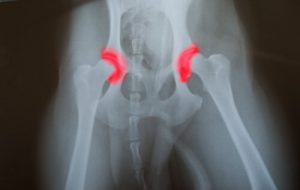

Cependant, si un chiot est suralimenté, il prendra du poids et grandira plus vite que ce qui est conseillé. En effet, cela provoquera une surcharge du squelette et peut ainsi entraîner les maladies suivantes :

- Osthéochondrite

- Dysplasie de la hanche

- Fragmentation et fissure du processus

Comparés aux grands chiens qui suivent un régime déséquilibré, ceux qui ont un régime équilibré présentent beaucoup moins de maladies. Ces maladies sont associées à une croissance excessive. Par exemple, la dysplasie de la hanche est l’une des maladies les plus courantes chez les grands chiens suralimentés.

Chez l’adulte, la suralimentation provoque une série de différents problèmes pour l’animal. En effet, la détérioration des articulations semble être une maladie plus répandue dans la population plus âgée.